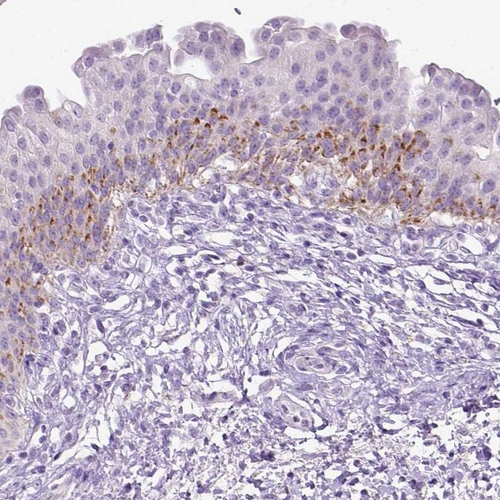

Immunohistochemistry analysis in human urinary bladder and fallopian tube tissues using HPA022261 antibody. Corresponding CYP24A1 RNA-seq data are presented for the same tissues.